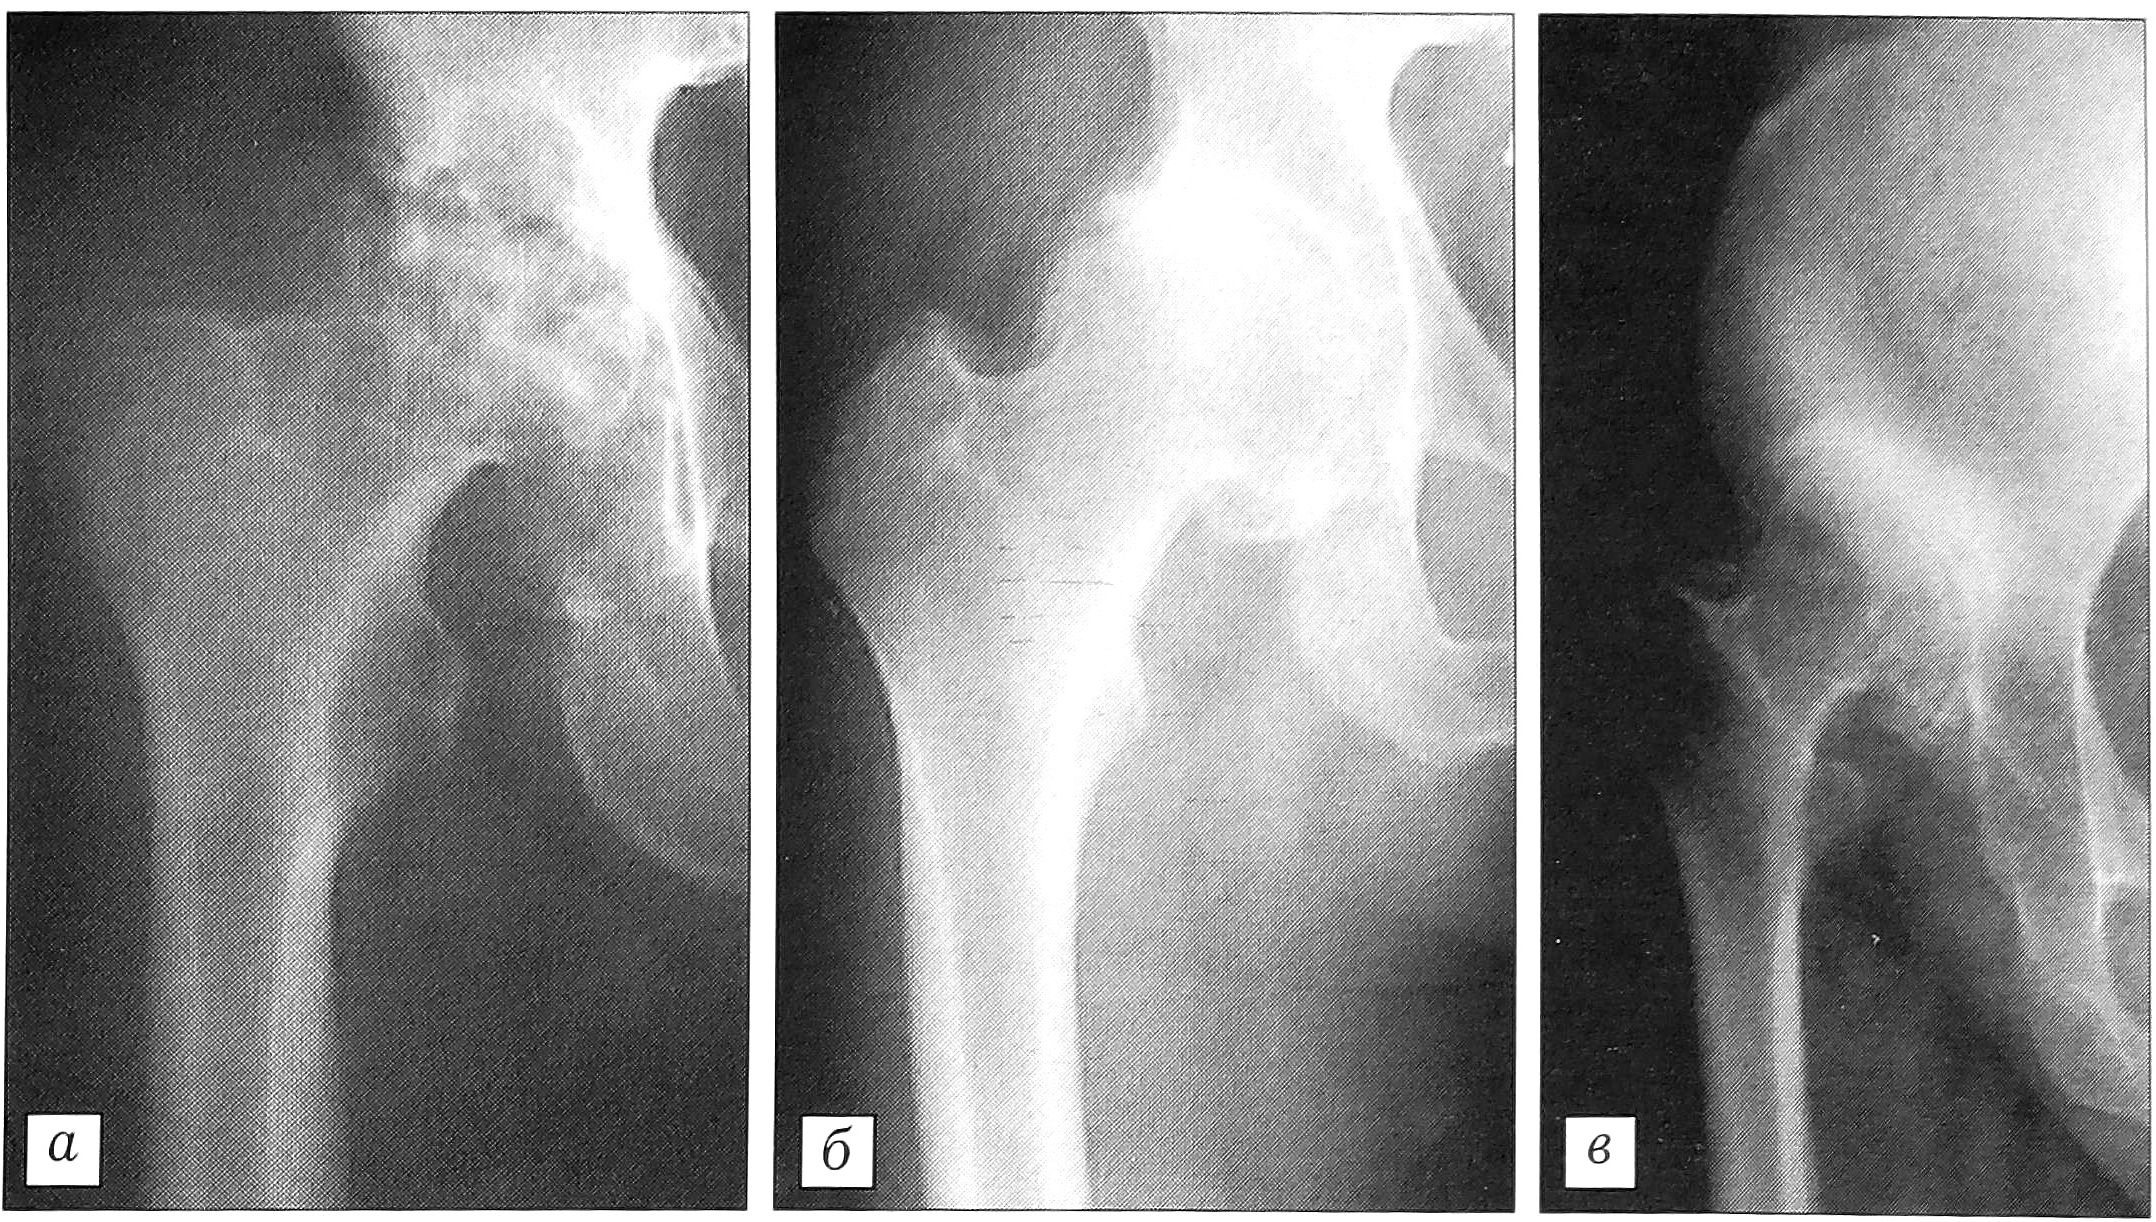

Выявлено достоверное численное преобладание пациентов с диспластической формой коксартроза над больными идиопатическим коксартрозом — соответственно 222 (87,4%) и 32 (12,6%) человека. Более чем у половины всех больных (144 пациента — 56,7%) имелась кистовидная перестройка костей тазобедренного сустава. При диспластическом коксартрозе кисты обнаружены у 137 (61,7%) больных, а при идиопатическом — только у 7 (21,9%). При I степени дисплазии кистозное поражение выявлено у 18 (24%) из 75 пациентов, при II степени — у 118 (85,5%) из 138 больных, при III степени кистозные изменения обнаружены лишь у одного (11,1%) из 9 пациентов. Таким образом, установлено достоверное преобладание случаев коксартроза с кистовидной перестройкой при II, наиболее часто встречающейся степени дисплазии тазобедренного сустава (рис. 2, а) и бескистозной формы коксартроза при 0,I и III степени дисплазии (рис. 2, б, в).

Рис. 2. Рентгенологическая картина коксартроза с разной степенью дисплазии тазобедренного сустава и наличием (а) и отсутствием (б, в) кистовидной перестройки костей. а — II степень, б — I степень, в — III степень дисплазии.